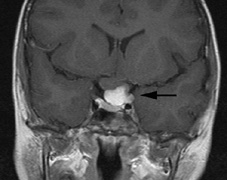

Optic nerve gliomas may involve the optic chiasm and be associated with endocrine disorders or nystagmus.68–70 Surgical excision of chiasmal gliomas (Fig. 6) carries a high risk of visual loss. Invasion of the hypothalamus or the third ventricle carries a poor prognosis, with greater than 50% 15-year mortality rate.71 One review of radiation treatment for chiasmal gliomas collated data from small case series and found no significant long-term improvement in visual function, progression, or mortality with radiation treatment.71 Other reports suggest that radiation doses over 4500cGy improve symptoms and slow progression of chiasmal gliomas over several years.72 Adequate tumor coverage by radiotherapy results in irradiation of normal brain and nearly all children need hormone replacement.73 Chemotherapy is an alternative.74,75

|